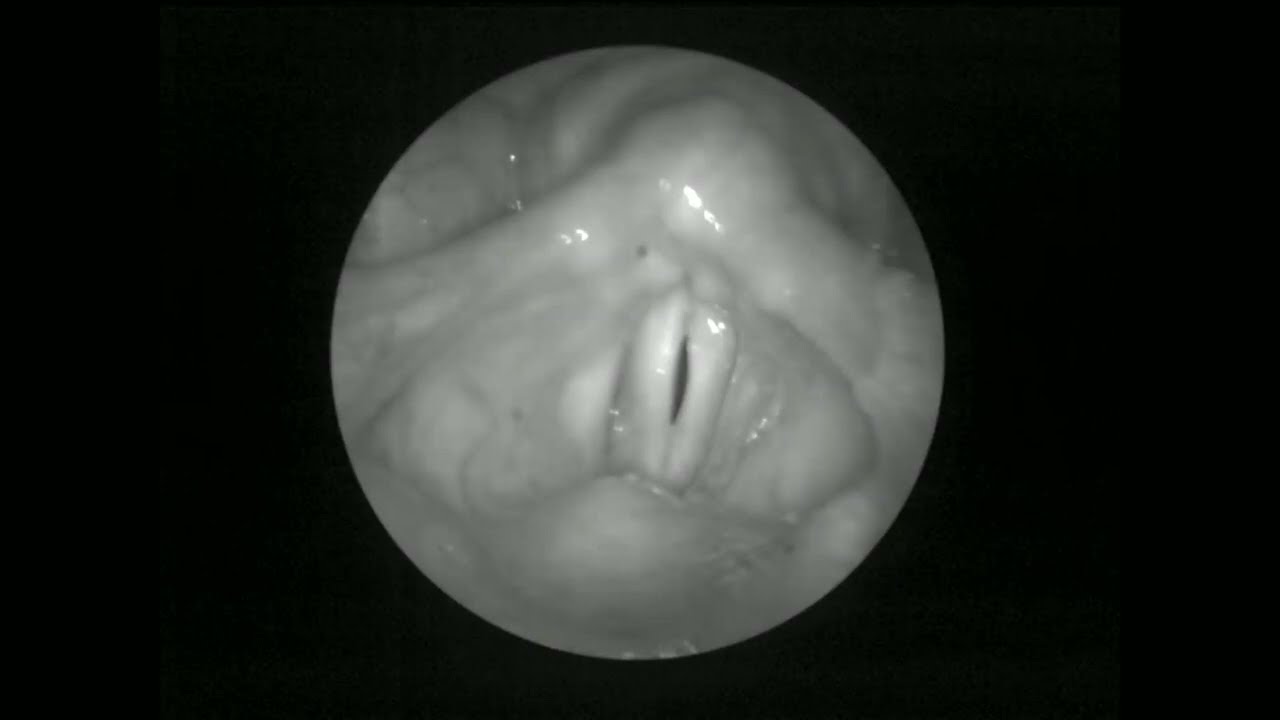

Высокоскоростная визуализация голосовых складок — это передовой метод, позволяющий запечатлеть вибрацию голосовых связок с предельной детализацией — до тысяч кадров в секунду. Она особенно полезна, когда стандартная видеостробоскопия не даёт достаточной информации, например, при нерегулярной или асимметричной вибрации, голосовом треморе или едва заметных рубцах, которые невозможно обнаружить при использовании более медленных методов визуализации. Этот метод идеально подходит для певцов, артистов и всех, у кого есть сложные или стойкие проблемы с голосом.

Процедура проводится в клинике и обычно занимает около 10–20 минут. Небольшой эндоскоп вводится через рот или нос во время выполнения вами определенных вокальных упражнений. Это безболезненно, но вы можете почувствовать небольшое давление или дискомфорт, особенно при использовании через нос — обезболивающий спрей помогает уменьшить эти ощущения. Сама процедура визуализации быстрая и безопасная, не требует седации и не требует времени на восстановление. После этого вы сможете разговаривать как обычно. Видео высокого разрешения даёт вашему врачу ценную информацию о точной механике вашего голоса и помогает разработать индивидуальный план лечения. Этот тест минимален по риску и часто дополняет другие исследования голоса, такие как стробоскопия или акустический анализ.